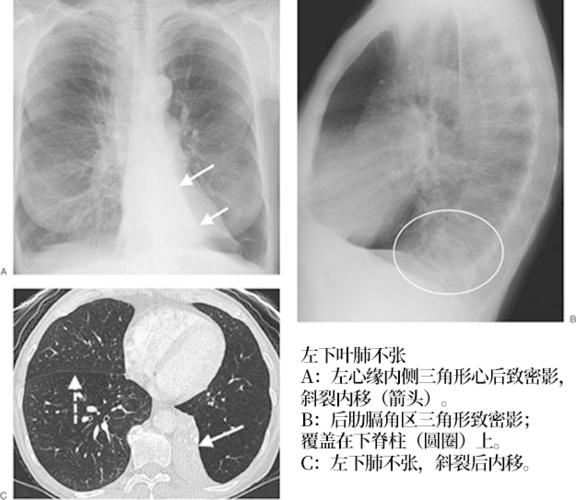

肺不张:影像基本思路